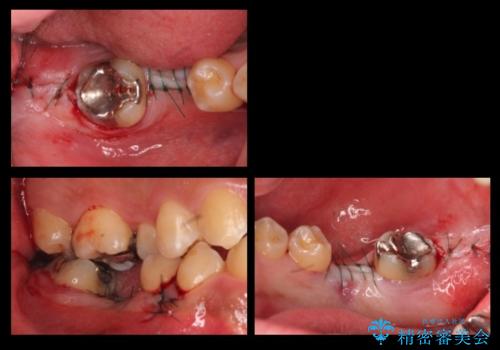

手術が怖いとのことで、外科手術時には静脈麻酔を行い、眠っている間に手術が終わるようにしました。

インプラントの術式は比較的単純で、難しくないですが、予後を見据えて角化歯肉を増やす手間をかけることが大変重要です。

インプラント手術時に同時に親知らずの抜歯も行い、腫れや痛みなどを1度で終わらせるようにしました。